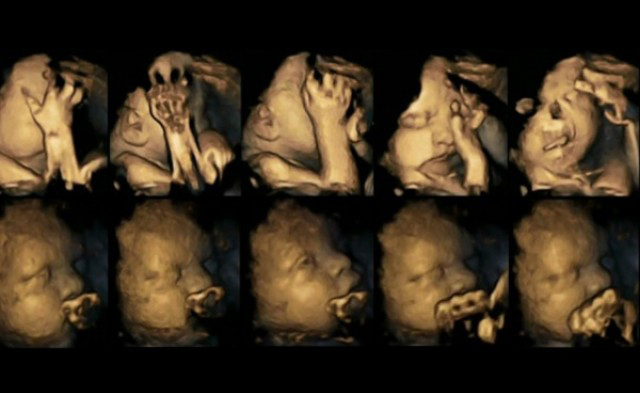

Secondo alcuni ricercatori, attraverso la visione di esami ecografici ad alta risoluzione, capaci di mostrare tutti i piccoli movimenti di un feto, è possibile rilevare gli effetti negativi che il fumo materno in periodo di gravidanza ha sul futuro neonato.

Feti sani iniziano a fare conoscenza con i propri arti e le diverse parti del corpo toccandosi la testa, sfiorandosi il viso, muovendo la bocca in molti modi. Tutti questi movimenti diventano meno frequenti quando il sistema nervoso centrale che controlla il movimento inizia a svilupparsi.

Un team britannico, guidato da Nadja Reissland della Durham University, ha osservato migliaia di movimenti della bocca e degli arti (circa 80 scansioni ecografiche in 4D) di 20 feti: 4 appartenevano a donne che fumavano in media quattordici sigarette al giorno, gli altri 16 erano di madri non fumatrici.

Le scansioni sono state prese a quattro diversi intervalli di tempo, compresi fra le 24 e le 36 settimane di gravidanza. Le donne hanno anche compilato questionari sul loro stato di stress o depressivo. “La tecnologia ci consente ora di vedere ciò che prima era nascosto, rivelando come il fumo influisca sullo sviluppo del feto in modi di cui non ci si era mai realmente accorti”, afferma Brian Francis della Lancaster University, co-autore della ricerca. “Questa è un’ulteriore prova degli effetti negativi del fumo in gravidanza”.

Tutti i bambini sono nati completamente sani. Tuttavia, i feti delle madri fumatrici hanno mostrato un tasso significativamente più alto di movimenti della bocca e degli arti, rispetto alla normale riduzione di movimenti prevista in un feto durante la gravidanza.

I ricercatori sostengono che la ragione di questa differenza potrebbe corrispondere a un significativo rallentamento dello sviluppo del sistema nervoso centrale dei feti di madri fumatrici: “Le immagini sembrano suggerire che i feti delle donne che fumano sono meno maturi nei loro comportamenti”, afferma Reissland all’USA Today.